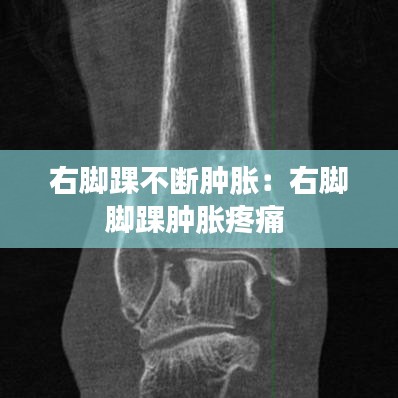

影像學檢查:如X光、MRI或超聲檢查,以排除骨折、關節損傷或其他結構性問題。